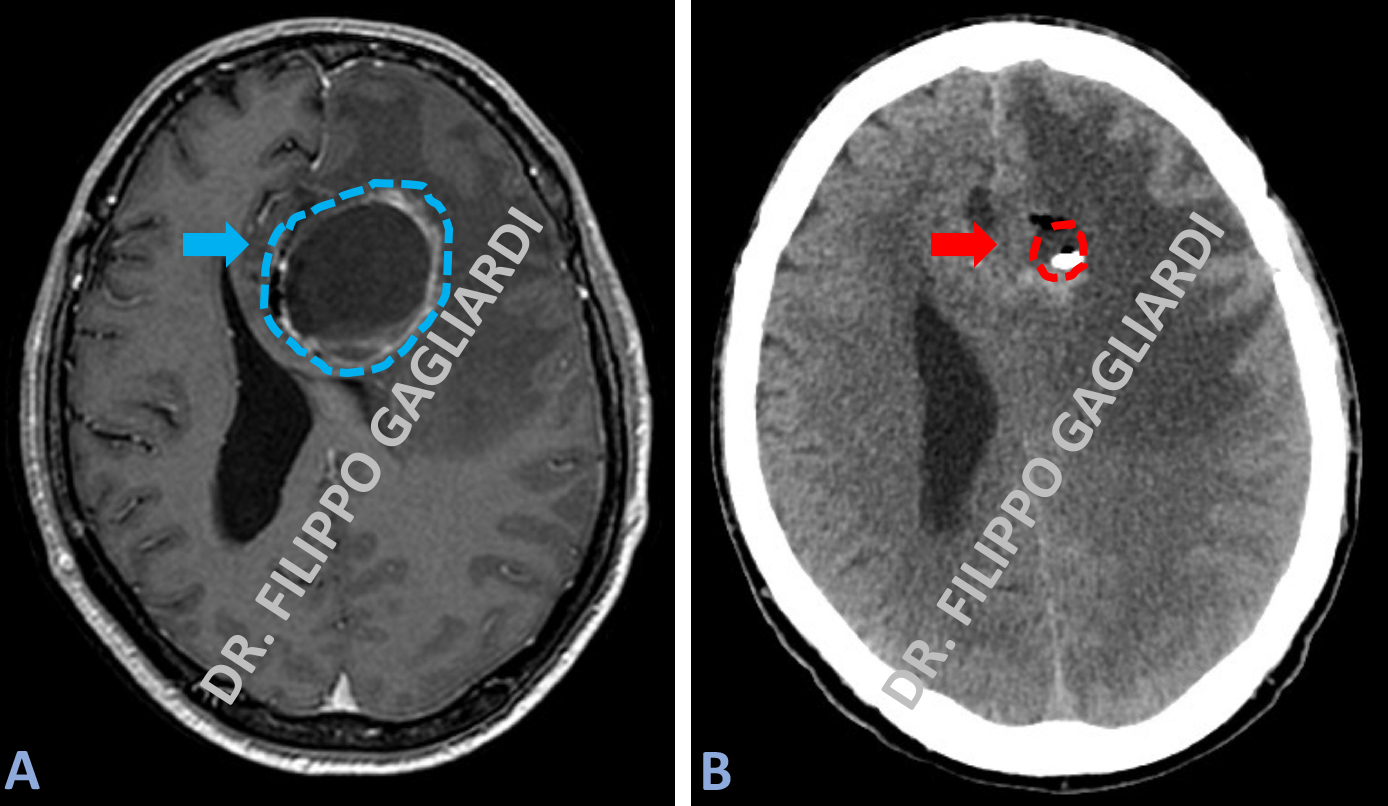

Si avvale di un casco stereotassico che viene montato sulla testa del paziente e che rappresenta un sistema di coordinate cartesiane per identificare una lesione intracranica con un precisione millimetrica. Un caso di drenaggio stereotassico di un tumore cistico (immagine azzurra tratteggiata, Figura A). Attraverso una piccola incisione in anestesia locale è stato inserito un piccolo catetere all’interno della cisti con una precisione millimetrica. Il liquido è stato quindi drenato senza aprire il cranio al paziente con il risultato di far scomparire la cisti (Figura B) e di risolvere l’aumento della pressione intra-cranica.